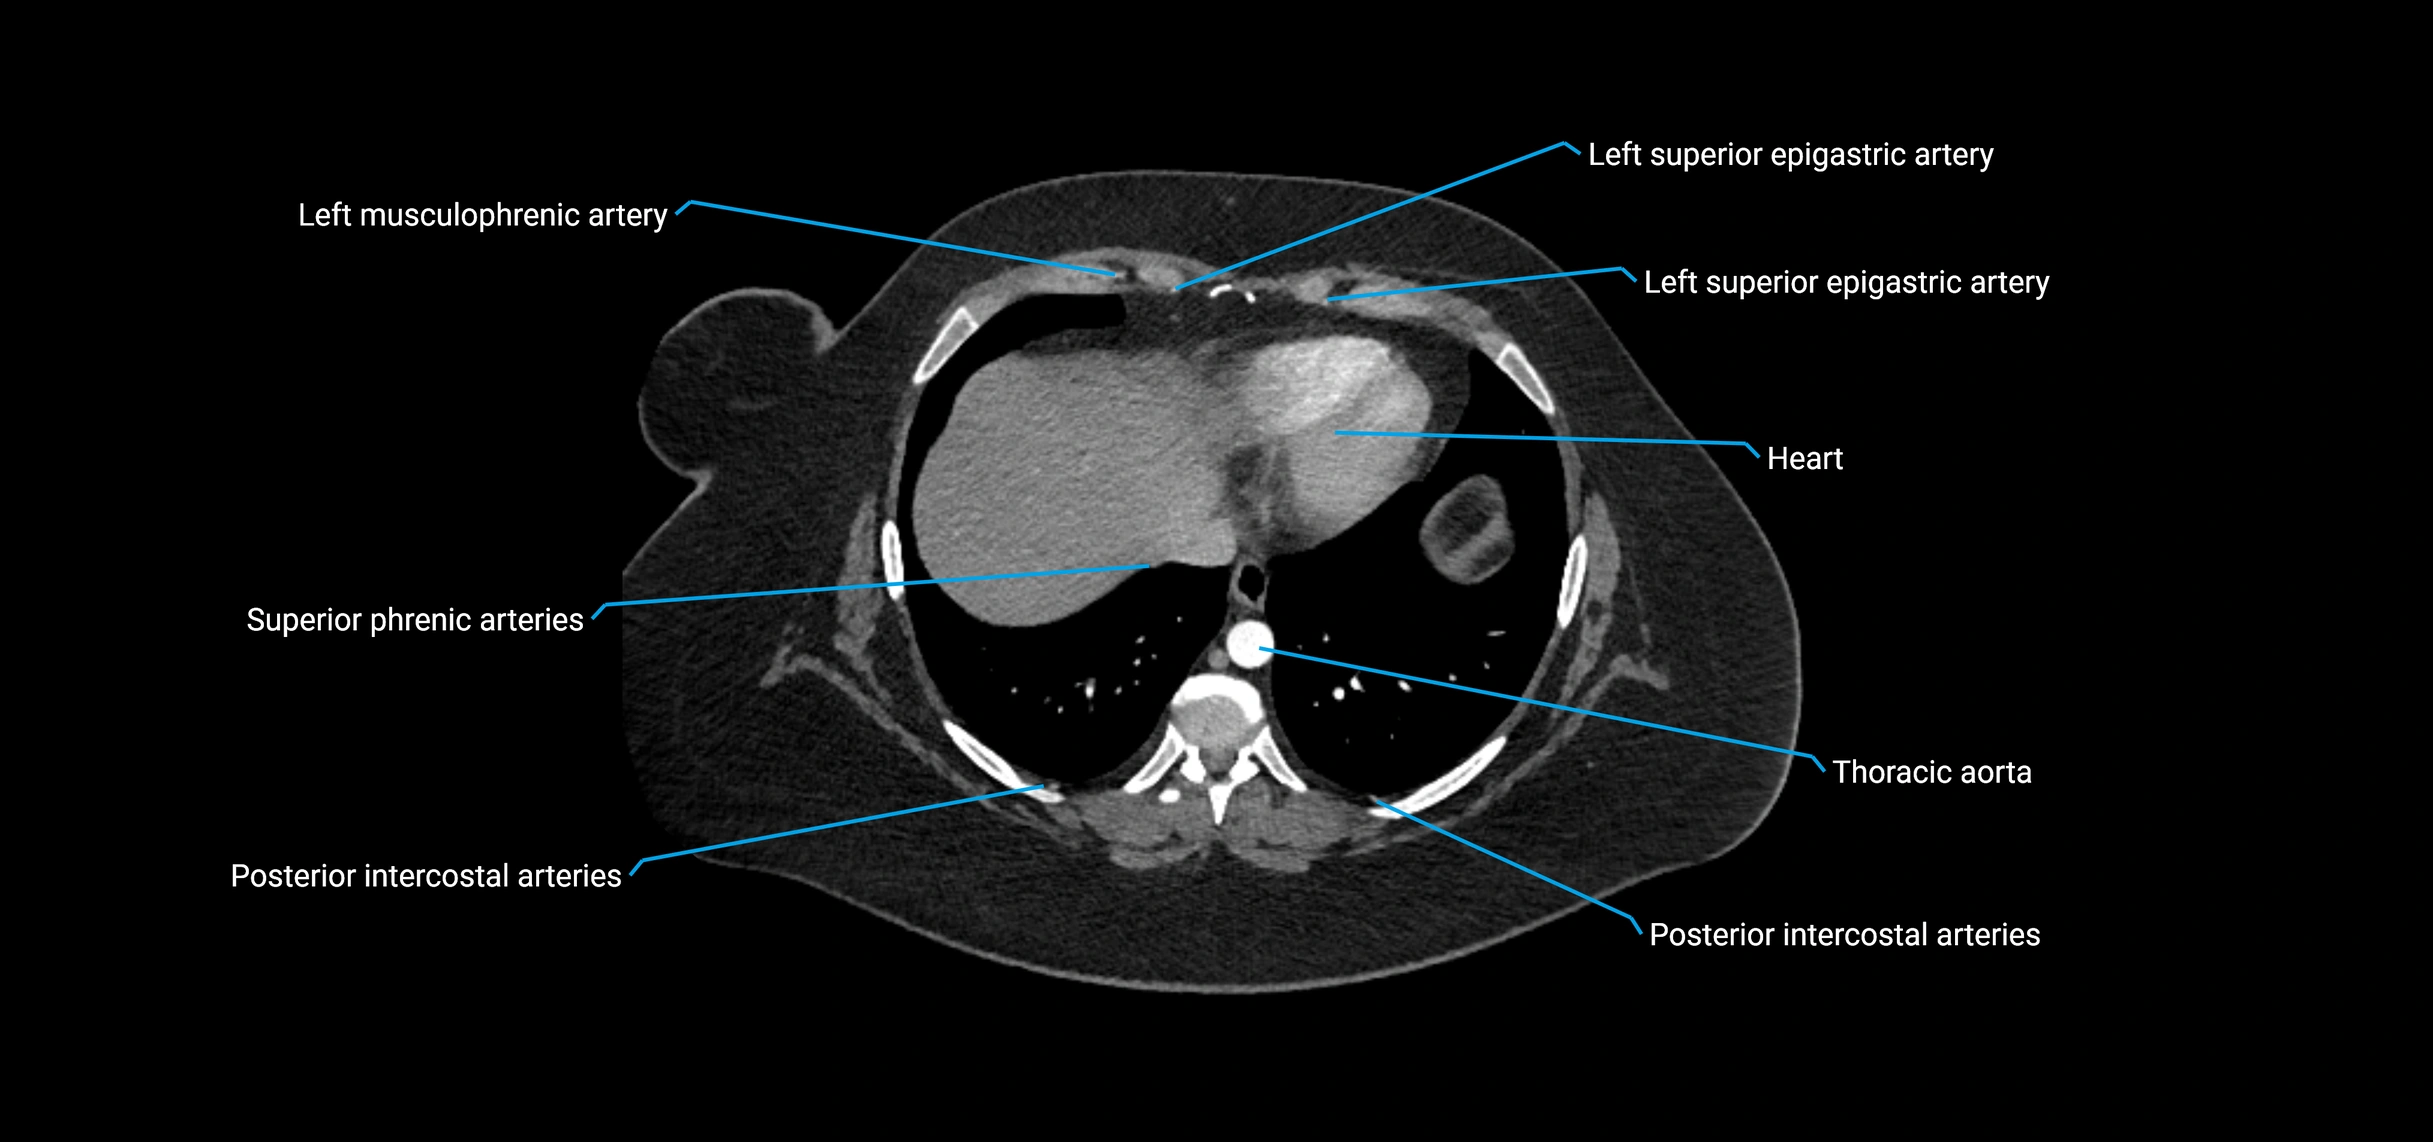

CT Appearance

Non-contrast CT:

• Appears as a tubular soft tissue structure anterior to vertebral bodies

• Calcified atherosclerotic plaques appear as hyperdense foci along the wall

• Useful for screening abdominal aortic aneurysm (AAA) size and mural calcification